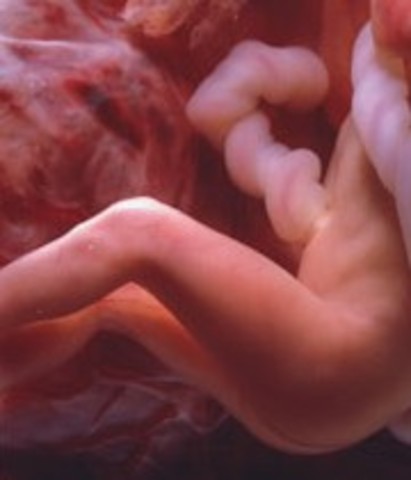

• Week Seven: Arms and legs begin to grow

Week Seven: Arms and legs begin to grow

The heart beat is in one chamber. The arms and leg buds start to grow.

• Week Eight: Starts to practice moving

Week Eight: Starts to practice moving

The legs and arms are growing and the elbow and toes are visible.The feet and hand buds appear.